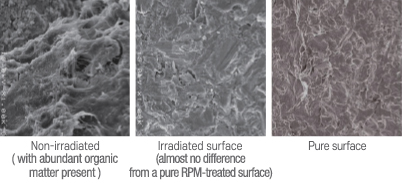

- Effective cleaning of contaminated implant surfaces

- No thermal damage to surrounding tissues

- Highly effective against bacterial infections

- No damage to the implant surface

- Promotes osseointegration and bone regeneration

Cross-sectional Comparison under Scanning Electron Microscope (×1000 Magnification)

Laser Sterilization Effect